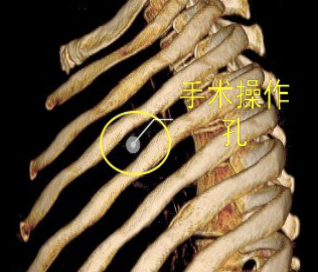

当前,绝大多数的肺大泡手术均可在电视胸腔镜(VATS)下完成,2/3的患者术后症状明显改善。与家长沟通后,邓意平成功为小王开展单孔胸腔镜下左侧肺大泡切除术。

较两孔、多孔胸腔镜手术或传统手术,单孔手术具有创伤更小、出血更少、术后疼痛更轻、瘢痕小、切口更加美观、术后恢复快、住院时间短等优势。但手术中所有器械(包括观察镜、吸引器、电凝钩、切割闭合器、双关节等各种操作器械)都要是从一个小“孔”进入,器械之间的互相干扰,同时器械与观察镜几乎平行,视野非常狭窄,手术难度明显,增加极其考验医生的技术。